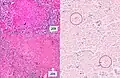

Histopathology, showing epithelioid granulomas with multinucleated giant cells and acid-fast bacilli